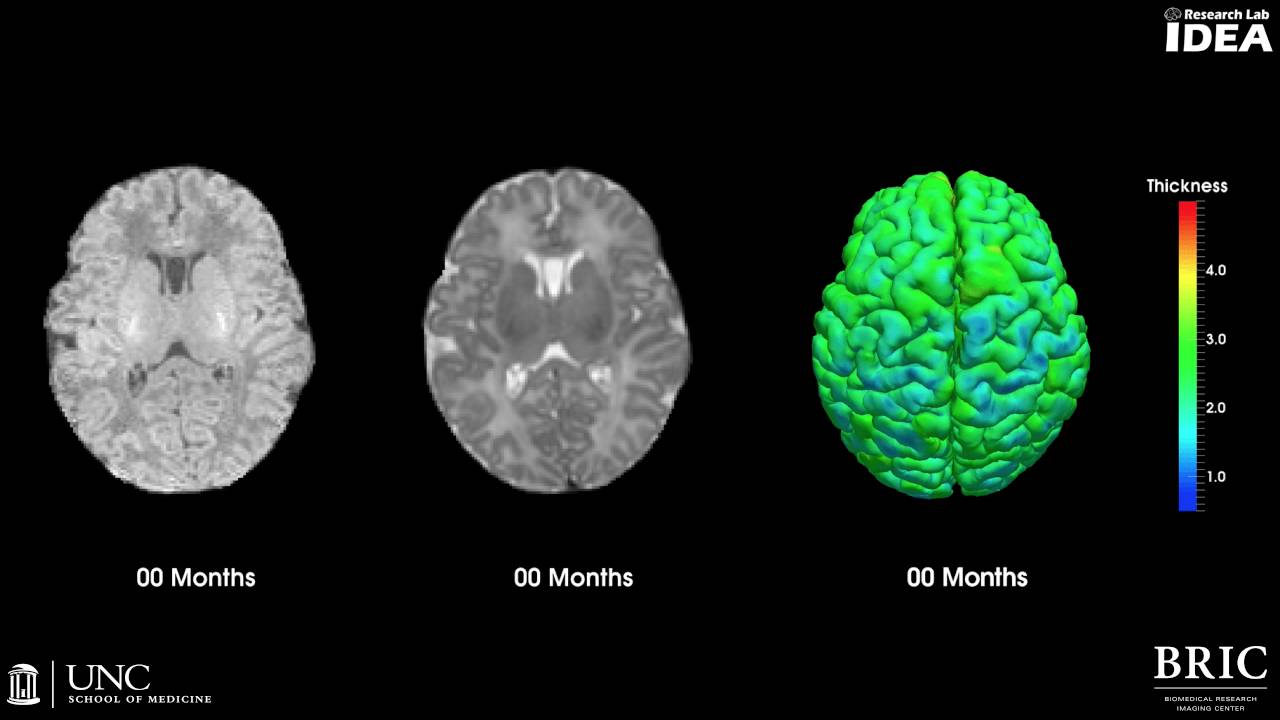

Brain Development In Infancy Free Return Www Pinnaxis Recent imaging studies have begun to delineate the growth trajectories of brain structure and function in the first years after birth and their relationship to cognition and risk for neuropsychiatric disorders. This image progression shows the brain development from birth to five years of one participant from dr. weili lin’s pilot study, the map brain imaging study.

Early Brain Development Diagram Quizlet In this study, we aggregated 1,091 resting state functional mri scans of typically developing children from birth to 6 years of age, harmonized the cohort and imaging state related bias, and. Caption this image progression shows the brain development from birth to five years of one participant from dr. weili lin's pilot study, the map brain imaging study. By two years, the human brain has grown to 80% of its original size. from this time, neurons and glia work together to refine the newly created synapses and circuits, a process that continues through adolescence. Brain development begins during pregnancy and reaches maturity around the age of three. proper nutrition is crucial for healthy brain development early in life and can have long lasting.